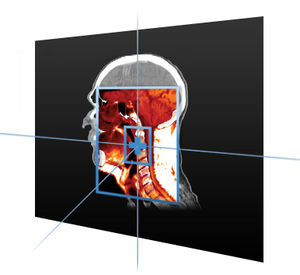

... Registro de imágenes para contorneado y evaluación de tratamientos previos Cuando los médicos completan los casos de uso en Maestro, crean mejores planes de tratamiento. Maestro sienta las bases para una mejor planificación del tratamiento mediante la ...